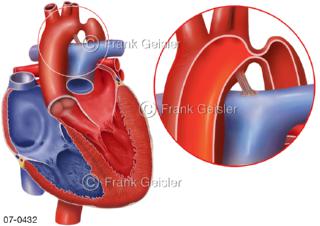

Bildergalerie Herz, Blutkreislauf

Bilder zu Herz, ein muskuläres Hohlorgan, das den menschlichen Körper durch rhythmische Kontraktionen mit Blut versorgt und dadurch die Durchblutung der Organe sichert, das Kreislaufsystem zeigt den Transport von arteriellem sowie venösem Blut durch das kardiovaskuläre System (Herz-Kreislauf-System), bestehend aus Blutgefäßen, Lymphgefäßen und dem Herz